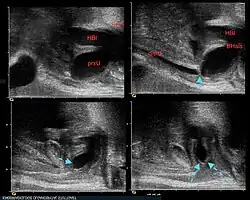

Bereits pränatal fallen im Ultraschall die große Harnblase mit verdickter Blasenwand, ggf. Erweiterungen an den Nieren, den Harnleitern oder eine zu geringe Fruchtwassermenge auf.

Nach der Geburt fallen die Kinder durch einen schlechten „stotternden“ Harnstrahl, im Ultraschall ebenfalls durch eine große Blase, verdickte Blasenwand und Erweiterungen an den Nieren und Harnleitern auf. Der direkte Klappennachweis ist sonographisch gleichfalls möglich.[2] Bei geringer Ausprägung der Klappen können die Kinder erst später durch Probleme beim Trockenwerden oder durch Harnwegsinfekte auffallen.

Die Diagnose wird aufgrund der charakteristischen Wandverdickung mit Unregelmäßigkeiten im Ultraschall gestellt und mittels Miktionszystourethrogramm bestätigt.